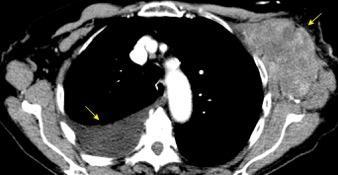

Masa axilar izquierda y derrame pleural derecho. Implantes pleurales, paraespinales . Ganglios en mamaria interna. Linfoma B difuso

Jaffe ES. Diagnosis and Classification of Lymphoma: Impact of Technical Advances.

2005. Masa pulmonar.